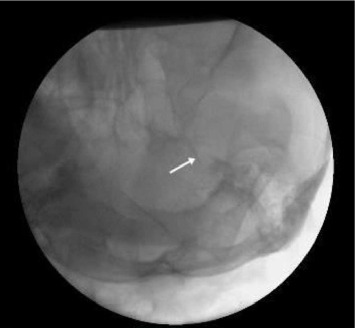

Abstract Image